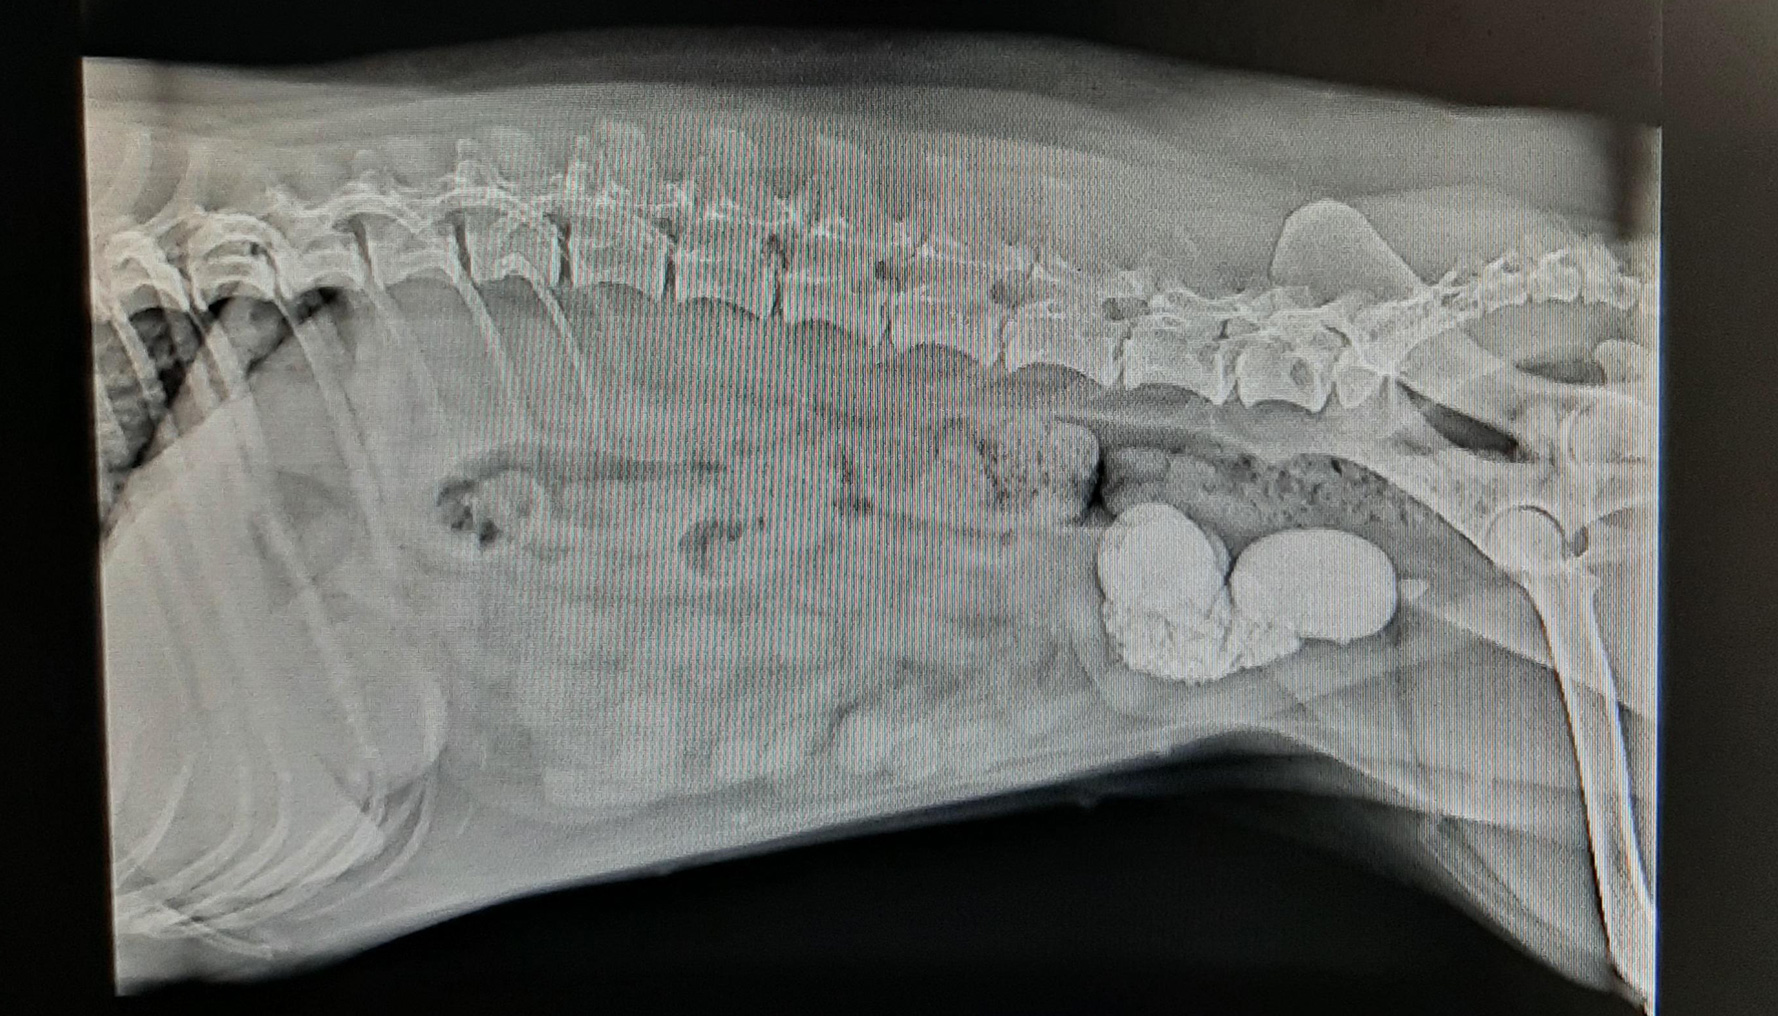

Cystotomy

Cystotomy surgery

Cystotomy is a surgical procedure in which an incision is made into the dog's urinary bladder. The procedure can be done for many reasons, the most common being to facilitate removal of bladder and urethral stones.